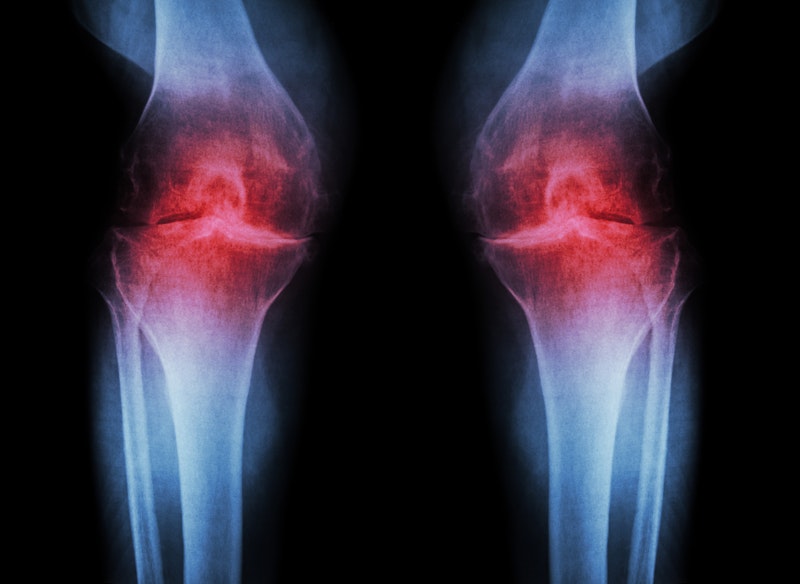

Деформирующий артроз голеностопного сустава — серьёзное заболевание опорно-двигательной системы, приводящее к снижению трудоспособности человека и возможной инвалидности. Этим термином обозначают также остеоартроз, деформирующий остеоартроз и некоторые другие заболевания.

Проявления деформирующего артроза разнообразны. Боли в области голеностопного сустава и мышц голени, опухание сустава, ограничение подвижности в нём, нарушение походки, ограничение ходьбы на длинные дистанции — вот лишь неполный список страданий, которые испытывает пациент с подобным заболеванием.

.Артрит голеностопного сустава может привести к боли, отеку, деформации и нестабильности голеностопного сустава. Артрит голеностопного сустава поражает большеберцово-таранный сустав, который формируется между большеберцовой костью (большеберцовой костью) и костью лодыжки (таранной костью).

Артрит — это общий термин для группы из более чем 100 заболеваний.Слово «артрит» означает «воспаление сустава». Артрит включает воспаление (отек) в суставах и вокруг них. Боль, скованность и отек могут быть результатом воспаления. Артрит может быть острым или хроническим воспалением сустава и окружающих его мягких тканей. При артрите происходит прогрессирующее ухудшение состояния суставов и постепенно утрачивается гладкий «амортизирующий» хрящ в суставах, что приводит к изнашиванию костей друг о друга. Мягкие ткани в суставах также могут начать изнашиваться. Артрит может быть болезненным и в конечном итоге может привести к ограничению движений, потере функции сустава и деформации пораженных суставов.

Наиболее распространенной формой артрита является остеоартрит, который обычно связан со старением. Другие факторы риска остеоартрита включают травмы суставов, ожирение, генетику и анатомические факторы, такие как форма и расположение суставов.

Как артрит влияет на стопу и голеностопный сустав?

В каждой стопе 28 костей и более 30 суставов. Наиболее распространенные суставы стопы, поражаемые артритом: